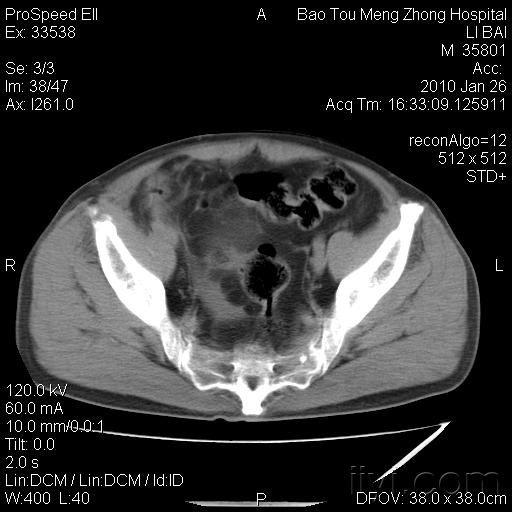

∩0∩ 急性阑尾炎别慌,不一定非得挨那一刀!急性阑尾炎的病理分型:决定治疗方向的关键 急性阑尾炎根据病理改变可分为不同类型,而类型差异直接影响治疗方式的选择。单纯性阑尾炎,炎症往往局限在阑尾黏膜和黏膜下层,阑尾外观可能仅表现为轻度肿胀,色泽稍显充血。此时,阑尾的病变相对较轻,尚未形成严重的化脓、坏疽或穿...

腹部剧烈疼痛竟是急性阑尾炎!医生:3个信号别忽视,早发现早治如果是症状较轻的单纯性阑尾炎,在医生评估后可以用抗生素进行保守治疗;但如果发展成化脓性、坏疽性阑尾炎,或者有穿孔的风险,及时手术切除阑尾就是最安全的选择。要知道,阑尾一旦穿孔,里面的细菌和脓液会扩散到整个腹腔,引发腹膜炎,严重时还可能导致感染性休克,后果不堪设想...